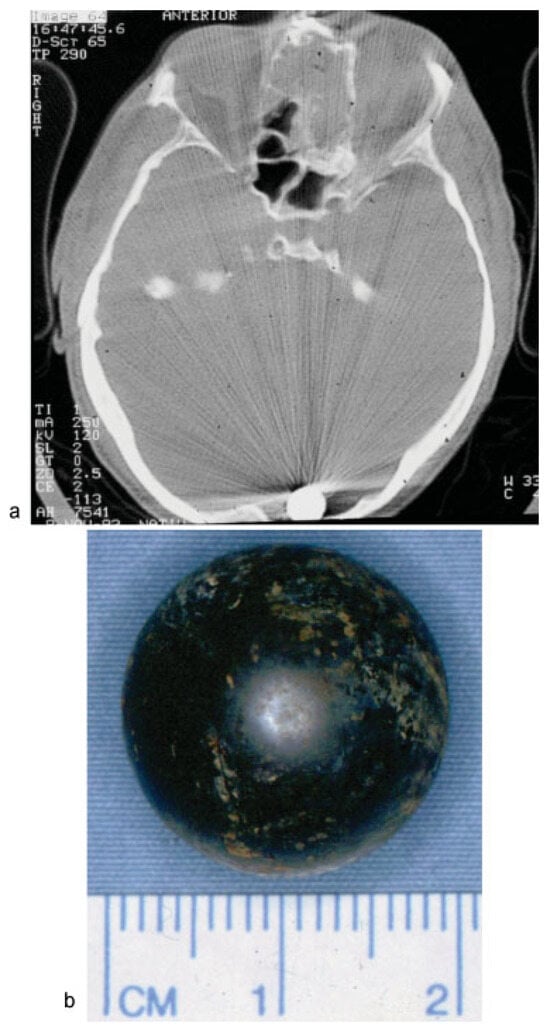

• Case 4: Another case of a foreign body caused by a gunshot was presented by a 63-year-old patient. Clinically, a single entry wound was detectable in the forehead, but there was no bullet exit wound. An MDCT scan revealed a single bullet close to the occipital bone, which had entered the cranium through the forehead, crushing the frontal sinus and ethmoid cells (Figure 4a). A bullet with a 2-cm diameter was removed by craniotomy in cooperation with colleagues from the neurosurgery department (Figure 4b). Wound therapy included debridement with large exposure of the frontal sinus, reconstruction and fixation of the anterior wall, and dura repair under a perioperative antibacterial regime. Shortly after removal, the patient was transferred to begin neurological rehabilitation.

Figure 4. (a) Intraoperative C-arm radiograph showing destruction of the ethmoidal bone with opacity, as well as a radiopaque intracranial foreign object close to the occipital bone. (b) Postoperative image of the removed bullet.